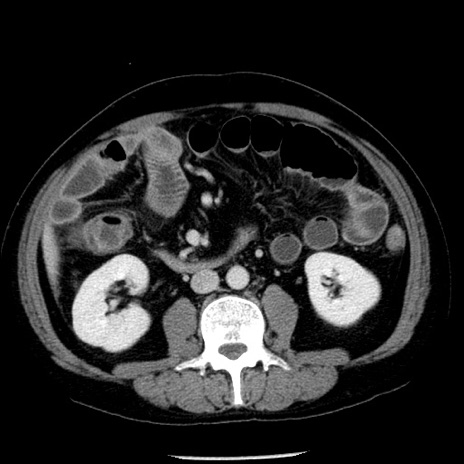

症例29(横断像)

【症例】40歳代男性

【現病歴】2日前から胃痛あり。徐々に周期的な激痛に変化した。本日になっても激痛があるため受診。

【身体所見】意識清明、BT 38-39℃台あり、腹部:膨満、やや硬、右下腹部に圧痛あり。

【データ】WBC 8500、CRP 23.26